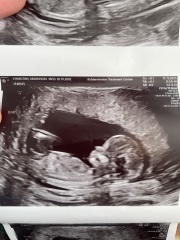

HerHeartJournals · 17/11/2025 14:05

The second one is a girl in my belief. My daughter’s scan showed her nub on the same angle. 🥰